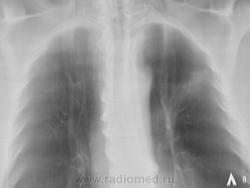

Направлен на рентгенографию ОГК с подозрением на пневмонию

Через 10 дней после проведения противовоспалительной терапии.

Группа очагов, сливающихся в инфильтрат. повторно прямых томограмм не было?

Всёж более похоже на посттуберкулёзные изменения.Точнее скажут фтизиатры после консультации.Необходим архив за прежние годы.

уж больно грубая деформация рисунка для инфильтрации?! ателектаз верхушечных сегментов по обзорным снимкам и доп. тень в области головки корня, в/долевой бронх не могу проследить монитор не позволяет наверное.

В корне как будто кругляк, но на тмг не видно, я бы онконасторожилась, возможно центральный рак растет

Я о субсегментарном ателектазе  в S 2 думаю. Бронхоскопию бы. Но сначала - АРХИВ!!!

Левый корень уплотнен, расширен за счет головки, ателектаз С 2, динамики нет. Думаю, более вероятно образование. Интересен анамнез, иначе зачем бы его лечили 2 нед а\б.

2013 год - "флюшка" - норма.

Анамнеза нет - контроль после проффлюшки

Если в архиве год назад-норма,версия постттуберкулёзных изменений снимается.Онкология на первом месте.

Присоединяюсь